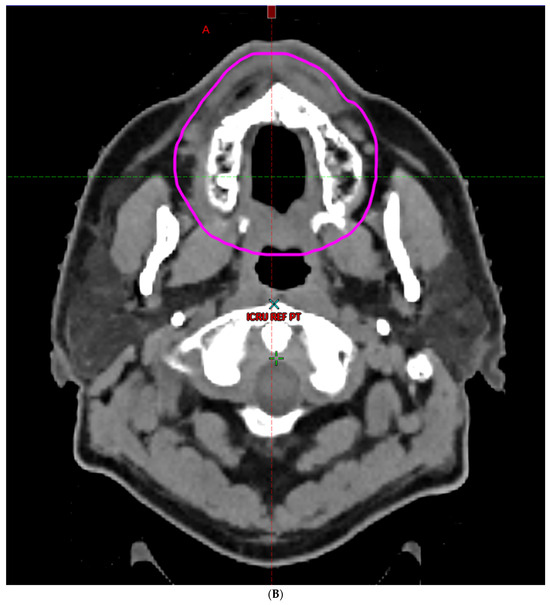

- Hoebers, F.; Yu, E.; Thorstad, W.; O’Sullivan, B.; Dawson, L.A.; Hope, A. A Pragmatic Contouring Guideline for Salivary Gland Structures in Head and Neck Radiation Oncology. The MOIST Target. Am. J. Clin. Oncol. 2013, 36, 70–76. [Google Scholar] [CrossRef]

- Brouwer, C.L.; Steenbakkers, R.J.; Bourhis, J.; Budach, W.; Grau, C.; Grégoire, V.; Van Herk, M.; Lee, A.; Maingon, P.; Nutting, C.; et al. CT-based delineation of organs at risk in the head and neck region: DAHANCA, EORTC, GORTEC, HKNPCSG, NCIC CTG, NCRI, NRG Oncology and TROG consensus guidelines. Radiother. Oncol. 2015, 117, 83–90. [Google Scholar] [CrossRef]

- Li, K.; Yang, L.; Hu, Q.-Y.; Chen, X.-Z.; Chen, M.; Chen, Y. Oral Mucosa Dose Parameters Predicting Grade ≥ 3 Acute Toxicity in Locally Advanced Nasopharyngeal Carcinoma Patients Treated with Concurrent Intensity-Modulated Radiation Therapy and Chemotherapy: An Independent Validation Study Comparing Oral Cavity versus Mucosal Surface Contouring Techniques. Transl. Oncol. 2017, 10, 752–759. [Google Scholar] [CrossRef]

- Sun, Y.; Yu, X.-L.; Luo, W.; Lee, A.W.; Wee, J.T.S.; Lee, N.; Zhou, G.-Q.; Tang, L.-L.; Tao, C.-J.; Guo, R.; et al. Recommendation for a contouring method and atlas of organs at risk in nasopharyngeal carcinoma patients receiving intensity-modulated radiotherapy. Radiother. Oncol. 2014, 110, 390–397. [Google Scholar] [CrossRef]

- Dean, J.A.; Welsh, L.C.; Gulliford, S.L.; Harrington, K.J.; Nutting, C.M. A novel method for delineation of oral mucosa for radiotherapy dose–response studies. Radiother. Oncol. 2015, 115, 63–66. [Google Scholar] [CrossRef]